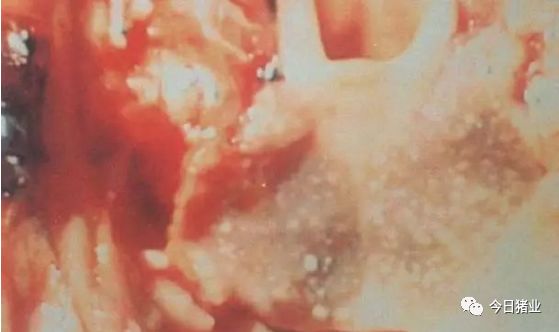

15.扁桃腺坏死性炎症

△【猪伪狂犬病】坏死性扁桃腺炎